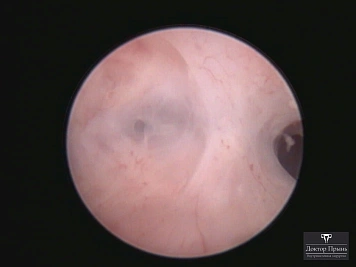

Как правило, синехии находят при УЗИ. Когда по УЗИ патологии нет, а симптомы есть, выполняют гистероскопию – это золотой стандарт в определении синехий.

Гистероскопия позволяет не только увидеть спайки, но и сразу вылечить, т.е. рассечь их. Большинству пациенток подойдёт офисная гистероскопия без наркоза и госпитализации. Среднее время операции 15 минут. Иногда требуется 2-4 операции, чтобы восстановить полость матки.

Крайне важен способ разделения спаек. Если это холодный инструмент, например, ножницы, то вероятность рецидива низкая. Плюс не повреждается нормальный эндометрий. Если рассекают горячей электропетлёй, то, наоборот, риск рецидива высокий и можно обжечь эндометрий.

Синехии, рассечённые Прынь Д.В.